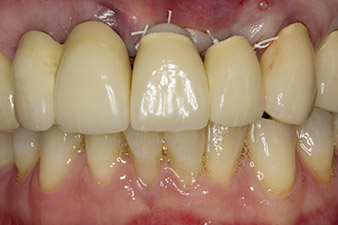

Fig. 1: The initial radiological findings revealed a splinted crown restoration requiring replacement. When the restoration was removed, teeth 21 and 22 were unintentionally extracted along with it.

The x-ray revealed horizontal bone loss around teeth 21 and 22 (Fig. 1). When the crown block was removed, these teeth were unintentionally extracted with it.